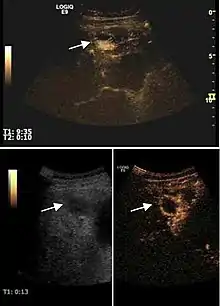

Hemangioma

It is the most common liver tumor with a prevalence of 0.4 – 7.4%. It is generally asymptomatic but also can be associated with pain complaints or cytopenia and/or anemia when it is very bulky. It is unique or paucilocular. It can be associated with other types of benign liver tumors. Characteristic 2D ultrasound appearance is that of a very well defined lesion, with sizes of 2–3 cm or less, showing increased echogenity and, when located in contact with the diaphragm, a "mirror image" phenomenon can be seen. When palpating the liver with the transducer the hemangioma is compressible sending reverberations backwards. Doppler exploration reveals no circulatory signal due to very slow flow speed. CEUS investigation has real diagnosis value due to the typical behavior of progressive CA enhancement of the tumor from the periphery towards the center. The enhancement is slow, during several minutes, depending on the size of hemangioma and on the presence (or absence) of internal thrombosis. During late (sinusoidal) phase, if totally "filled" with CA, hemangioma appears isoechoic to the liver. Deviations from the above described behavior can occur in arterialized hemangiomas or those containing arterio-venous shunts. In these cases, differentiation from a malignant tumor is difficult and requires other imaging procedures, follow up and measurements of the tumor at short time intervals.[4]